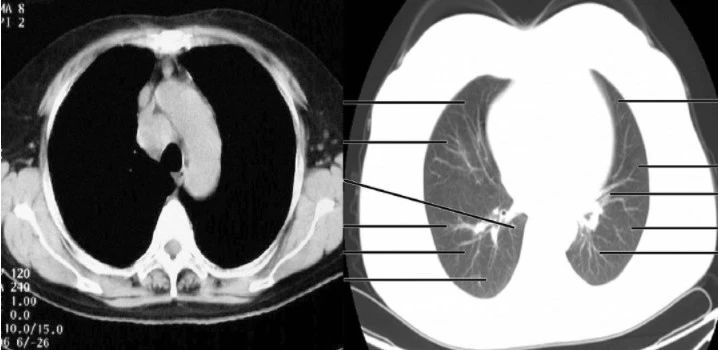

以上两张图,都是显示的胸部,左图可以看到纵隔(心脏等)内的一些细节,右图可以清晰地看到肺部的气管,支气管,纵隔内则是白茫茫一片。这就是调整对比度的结果。